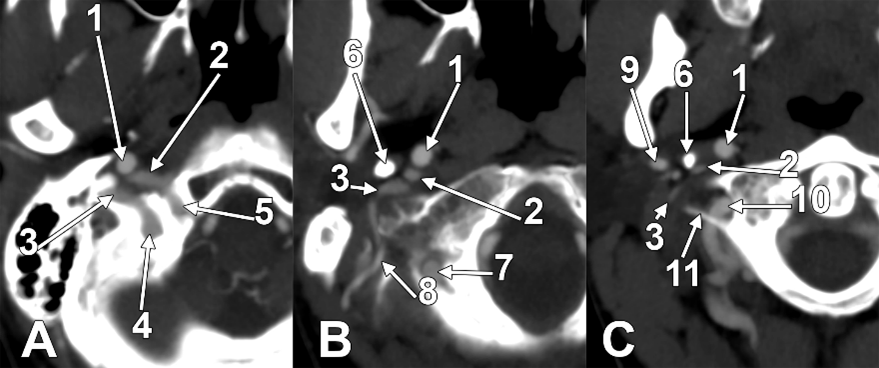

Figure 7. Successive axial sections from superior to inferior (AC) through the long inferior petrosal sinus. Right side. Inferior views. 1. Internal carotid artery; 2. inferior petrosal sinus; 3. internal jugular vein; 4. sigmoid sinus; 5. anterior condylar vein; 6. styloid process; 7. vertebral artery; 8. occipital artery; 9. external carotid artery; 10. vertebral artery; 11. transverse process of the atlas.

On the right side (Figure 7 and Figure 8), a 4.23 cm long styloid process was found, with a medial inclination of 72.4°. It crossed anteriorly, above the transverse process of the atlas, two veins: laterally—the internal jugular (IJV) vein, which had a transverse diameter of 5.94 mm, and medially—a long inferior petrosal sinus (IPS), with a transverse diameter of 3.15 mm. The IJV continued laterally to the transverse process of the atlas, and the inferior petrosal sinus, anterior to it. It was observed that the compression of the IJV occurs between the transverse process of the atlas and the posterior aspect of the digastric muscle. Also, the IPS appeared compressed at this level. The IJV had a minimum diameter of 1.21 mm, and the IPS had a minimum diameter of 1.08 mm. The IPS crossed laterally the ICA and APA, which, in turn, originated from the ICA (type IV), and continued medial to the ECA, crossed the origin of the FA, and descended anterior to the ECA, over the initial loop of the LA. The IPS and ECA coursed on the lateral side of the greater hyoid horn. Inferior to the hyoid, the IPS crossed the STA laterally and continued obliquely posteroinferiorly over the CCA, emptying into the IJV at 3.59 cm inferior to the CB. The APA on that side arose from the anteromedial wall of the origin of the ICA, at the hyoid level.